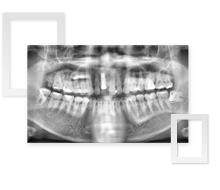

以上顎竇骨增高術、再生膜、骨引導再生術進行人工植牙

患者口內有多顆牙齒皆為傳統牙冠且右、上下方嚴重缺牙,深感不便,因此前來梵谷美學牙醫診所就診。經過醫師仔細評斷與分析,建議併同上顎竇骨增高術並放置再生膜,引導骨再生,以建立完善骨質環境。